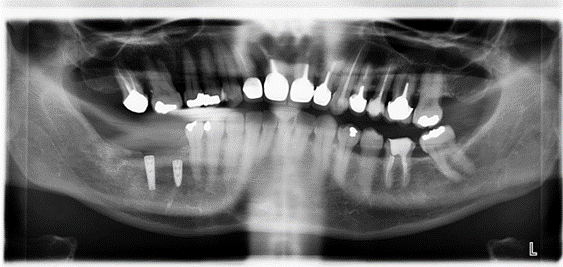

La perte des dents dans les secteurs postérieurs de la mâchoire supérieur peut aboutir à une résorption osseuse sous la pression du sinus, dont l’expansion n’est plus limitée par la présence des dents. Ce phénomène a pour nom la pneumatisation du sinus.

La hauteur d’os nécessaire à la pose d’un implant peut donc vite se trouver insuffisante. Pour rétablir les critères biologiques et fonctionnels de le chirurgie implantaire, nous procédons à une greffe sinusienne, ou sinus lift.

Cette chirurgie de précision, consiste à effectuer une fenêtre osseuse latérale pour accéder à la membrane qui tapisse la cavité sinusienne, décoller cette dernière de façon suffisante, pour ménager un espace qui sera comblé avec de l’os. Il est nécessaire d’attendre 4 mois de consolidation avant de procéder à la chirurgie implantaire.

L’extraction implantation mise en charge immédiate

Cette procédure chirurgicale a pour objectif de conserver l’anatomie et la structure des tissus situé dans l’environnement de la dent extraite (os et gencive). Ainsi lors de l’ostéo intégration de l’implant la résorption de l’os et la gencive sont limitées. La restauration prothétique se trouve alors parfaitement intégrée à son environnement.